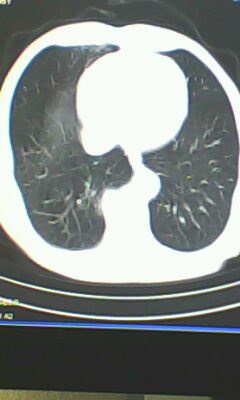

胸廓呈桶状,双膈低平,肺实质及纵隔未见明显异常密度灶考虑肺气肿.

肺气肿

以下是引用ctkz987在2010-5-5 21:30:00的发言:[br]胸廓呈桶状,双膈低平,肺实质及纵隔未见明显异常密度灶考虑肺气肿.

做个肺功能检查。肺ct无明显异常。

弥漫性肺气肿 但内胆管轻度扩张

临床诊断:copd

慢阻肺是临床诊断,未见明显异常。